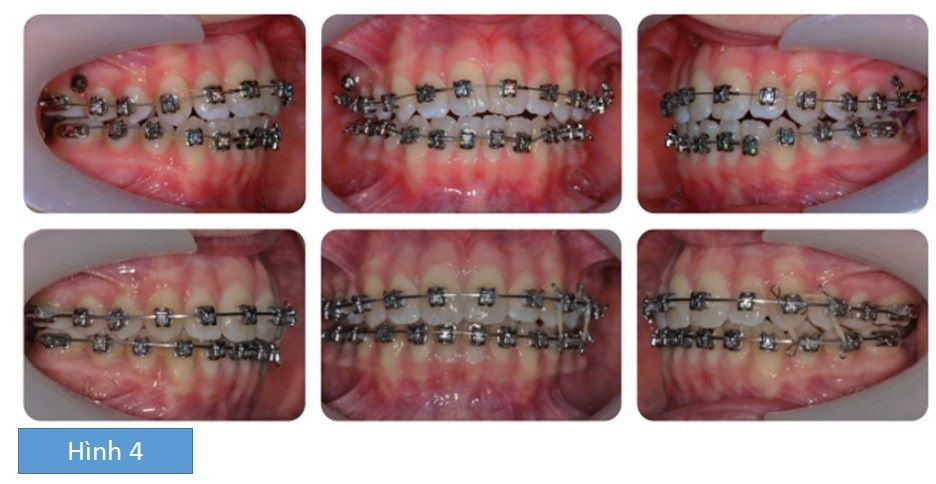

Mục đích của điều trị là giảm chen chúc, làm đều và làm phẳng 2 cung hàm, sửa chữa cắn chéo và cắn hở phía trước, để đạt được tương quan răng cửa và răng hàm hạng I. Tình trạng cắn chéo ban đầu được sửa chữa bằng cách sử dụng khí cụ tháo lắp hàm trên với vít nong ở giữa. Phần chụp (capping) ở mặt ngoài ở các răng sau được thiết kế để tránh làm tồi tệ hơn cắn hở phía trước khi nong rộng hàm trên. Một khi cắn chéo được sửa chữa, cả 4 răng hàm lớn thứ hai được nhổ và máng đánh lún tùy chỉnh được gắn lên mặt nhau của các răng sâu hàm trên, cùng với chụp (capping), và gắn 2 cung khẩu cái đặt cách khẩu cái vào. Từng ốc vít nhỏ được gây tê và cắm vào 2 bên giữa chân răng của răng tiền hàm thứ hai và răng hàm lớn thứ nhất phía ngoài (Absoanchor 7mm x 1.4 mm). Lực đánh lún được đặt tác động lên răng bằng cách dùng lò xo Niti đã kích hoạt gắn vào mini-vít. Mini-vít bên phải lỏng và được thay thế bằng minivit thứ 2 (Infinitas 9mm x 1.5mm). Khi đạt được hiệu quả đánh lún, máng đánh lún được tháo ra và hệ thống khí cụ edgewise sẵn thông số hàm trên và hàm dưới được gắn vào. Các răng được làm đều và làm phẳng và có độ cắn trùm dương và cắn chìa dương. Khi khí cụ cố định được tháo bỏ, khí cụ duy trì dán dính hàm dưới được gắn vào và được bổ sung với hàm duy trì máng nhựa phủ mặt nhai ép chân không để đeo vào ban đêm.